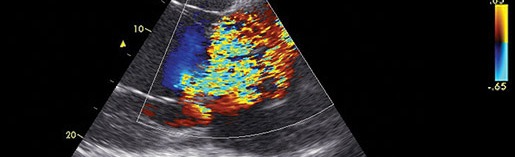

Gunther van Loon graduated from Ghent University, Belgium, in 1992 and has worked at the Ghent University, Department of Large Animal Internal Medicine, ever since. In 2001 he finished his PhD on “Atrial pacing and experimental atrial fibrillation in equines”. In 2004 he became Diplomate of the European College of Equine Internal Medicine and in 2011 Associate Diplomate of the European College of Veterinary Diagnostic Imaging. In 2015 he received the Merial Applied Equine Research Award for outstanding research regarding ‘Advances in Equine Cardiology’, awarded by the WEVA. He is Full Professor in Large Animal Internal Medicine at Ghent University and his major interests are all aspects of cardiology, and thoracic and abdominal ultrasound. Areas of research include advanced imaging (speckle tracking, tissue Doppler, 3D, intracardiac echo), biomarkers, vascular disease, and arrhythmias and electrophysiology (atrial tachycardia/fibrillation, 3D mapping, ablation). Gunther has published mainly in the field of equine internal medicine and cardiology and lectures regularly at national and international courses and conferences.

Advanced Equine Cardiology – A 2-Day Practical Boutique Course (max. 25 vets)